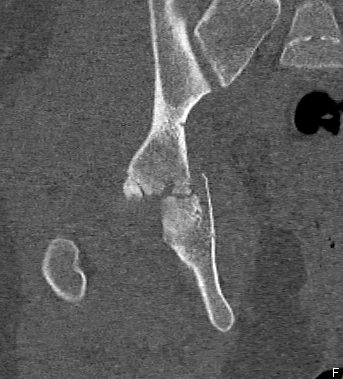

CT

Configuration

1-2 mm sections

CT reconstruction

- remove head to view acetabulum

- beware volume averaging

- used to guide surgery

Diagnose

Loose bodies

Femoral head fractures

Subtle subluxation

Articular steps

Roof arc measurement